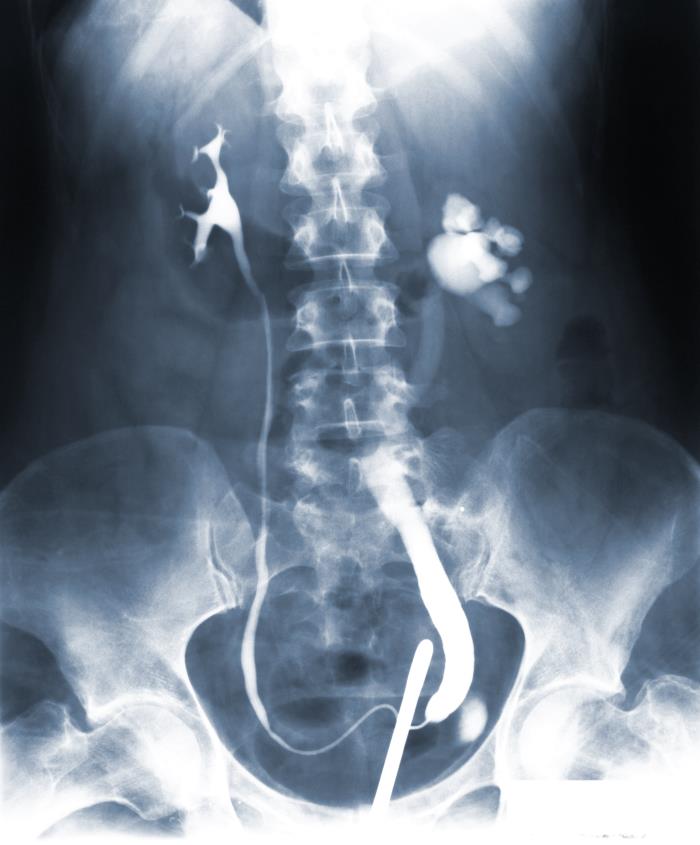

After having introduced radiopaque dye into the right and left ureters, by way of a procedure known as a retrograde urogram, this posteroanterior (PA) pelvic x-ray was executed, revealing pathologic changes in this Rome, Georgia tuberculosis patient’s right kidney. Note the abnormal dilatation of the right renal calyces, known as asymmetrical hydrocalycosis, as well as a dilated right ureter. The left kidney’s pelvis, and ureter, appeared to be normal. These findings are highly suggestive of a disease process known as renal tuberculosis, which was, indeed, the case.